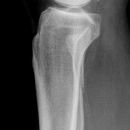

distaler Unterschenkelschaft

Spiralfraktur Tibia